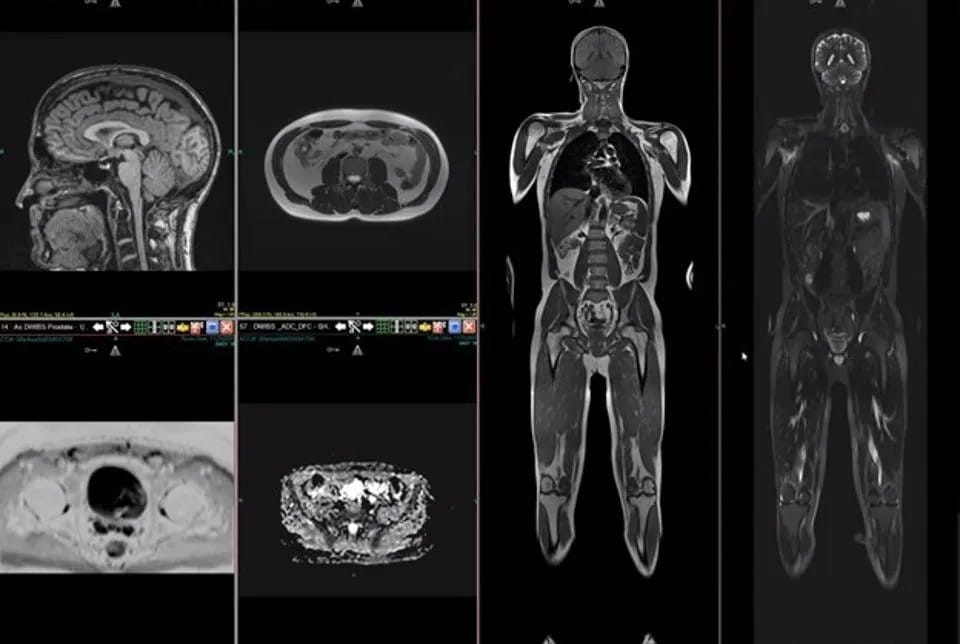

Full Body MRI Scan

A Full Body MRI is a powerful, radiation-free scan that provides a detailed view of your entire body. It helps detect potential health issues early, offering clear insights into your organs, tissues, and bones – all without invasive procedures.

A Full Body MRI uses powerful magnets and radio waves to create highly detailed images of your entire body. Unlike X-rays or CT scans, it’s completely radiation-free, making it a safe and effective way to assess your internal health. This scan can detect tumours, inflammation, or early signs of disease – even before symptoms appear.

By capturing a detailed view of key areas, including the brain, spine, abdomen, and pelvis, a Full Body MRI offers a comprehensive look at your overall well-being.